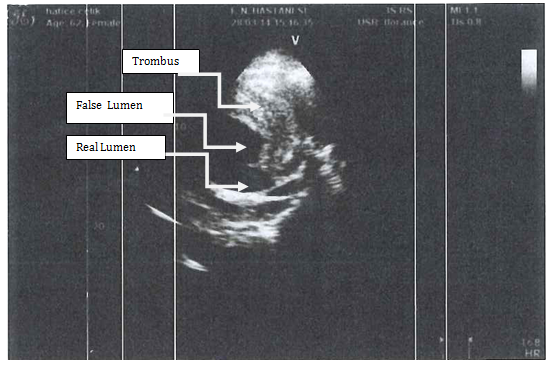

A 62-year-old female patient with known hypertension, obesity history was referred to the cardiology polyclinic by inhalation and diuretic therapy after examination of her chest diseases polyclinic with shortness of breath and rapid fatigue. Blood pressure was measured 130/80 mmHg in both of arm, pulse was 114/m and irregular. Periferal pulses were fuller, faster, arrhtymic on all extremity. Heart sounds were heard as a 3/6 diastolic murmur in aortic focus and 2/6 systolic murmur in mitral focus. Respiratory sounds were normal and equal in both of hemithorax. Hyperlipidemia, impaired fasting glucose, normal renal function were detected in laboratory tests. In echocardiographic examination was revealed ejection fraction %32, mild mitral and tricuspid regurgitation, modarete aortic regurgitation and degeneration at both of valves, aneurismatic dilatation in ascending aorta (9.1 cm) and aortic arch (5.4 cm) were revealed (Figure 1). There was seen dissection fleb in proximal ascending aorta and thrombus was observed in false lumen. Afterwards, that patient was scaned by thoracoabdominal computerized tomography angiography. Diameter of aneursym was measured 9.8 cm and it was extending to the arch aorta (Figure 2 & 3). Dissection and plaque were not seen on carotid doppler ultrasonography. Coronary angiography was not applied to patient before surgery operation because of high risk. Supracoronary Graft Interposition and Hemiarchus Replacement was applied to patient after preparations were completed (Figure 4 & 5). Prostetic aortic valve replacment was not performed to patient because of there was no pathology other than degeneration. Control echocardiography was performed after intensive care process. Ejection fraction was measured %55 and seen mild mitral-aortic-tricuspid regurgitation. The patient was discharged after 6 days without any problems in the postoperative period.

Figure 2: Computerized Tomography Angiography Image of Ascending Aort Aneursym with chronic dissection.

Even though abdominal aortic aneursym is seen the most frequently, thoracic aortic aneursym have different importance because of it is quite as development of rupture and dissection clinic. Early diagnosis and treatment prevent from mortality. In the recently published European Cardiology Society Guide to Aortic Diseases (2014) surgical borders are as follows; 45 mm in patients with Marfan's syndrome, 50 mm in patients with bicuspid aortic valve and 55 mm in the other patient group [4]. In our patient, the diameter of ascending aorta was measured as 98 mm in the widest place. Thoracic CT angiography provides us with the most accurate results in terms of assessing how far and where the aneurysm has been measured and how far it has been measured, even though echocardiography is required routine evaluation in outpatient. We also want to emphasize the importance of multimodality imaging in this case.